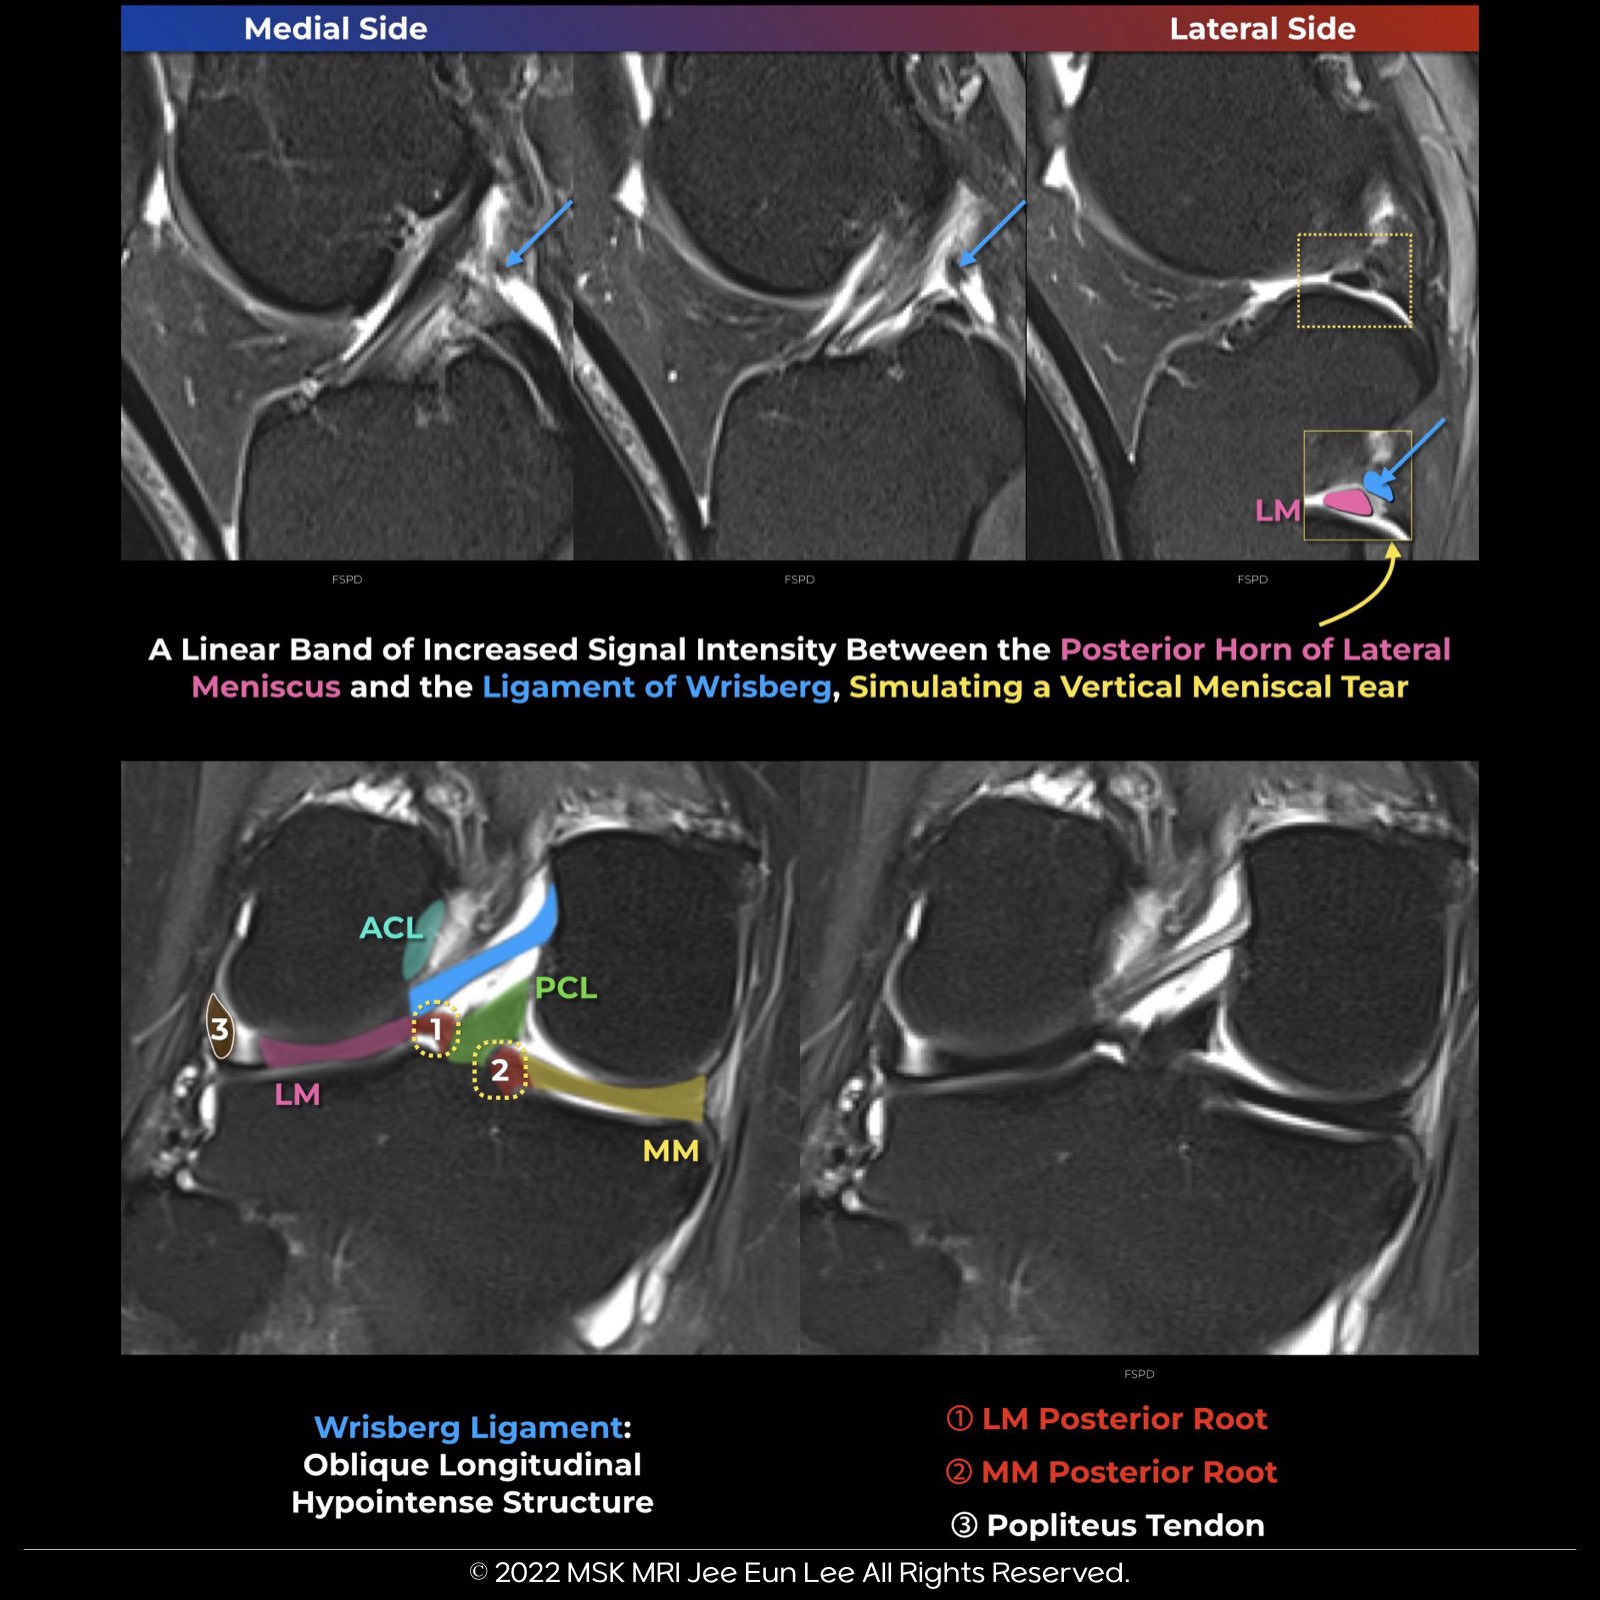

The posterior meniscofemoral ligament in the knee connects the medial femoral condyle to the posterior horn of the lateral meniscus. It runs posterior to the posterior cruciate ligament (PCL) and attaches above the PCL. This ligament is positioned more posteriorly compared to the anterior meniscofemoral ligament, which attaches below the PCL.